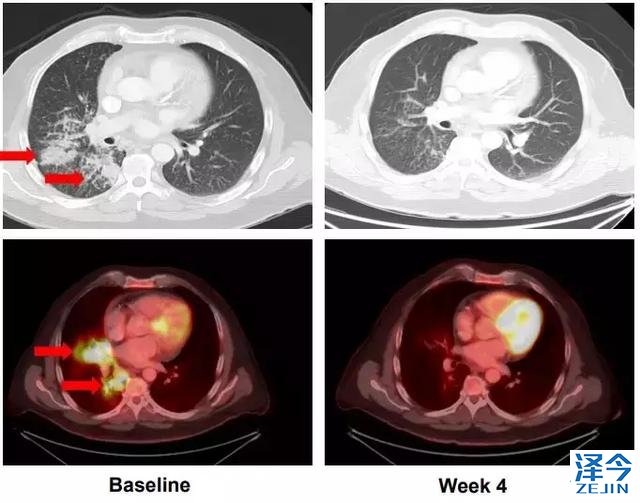

另一位52岁的肺癌患者,化疗耐药之后进行基因检测发现具有KIF5B-RET基因融合,使用LOXO292 4周之后肿瘤显著缩小。